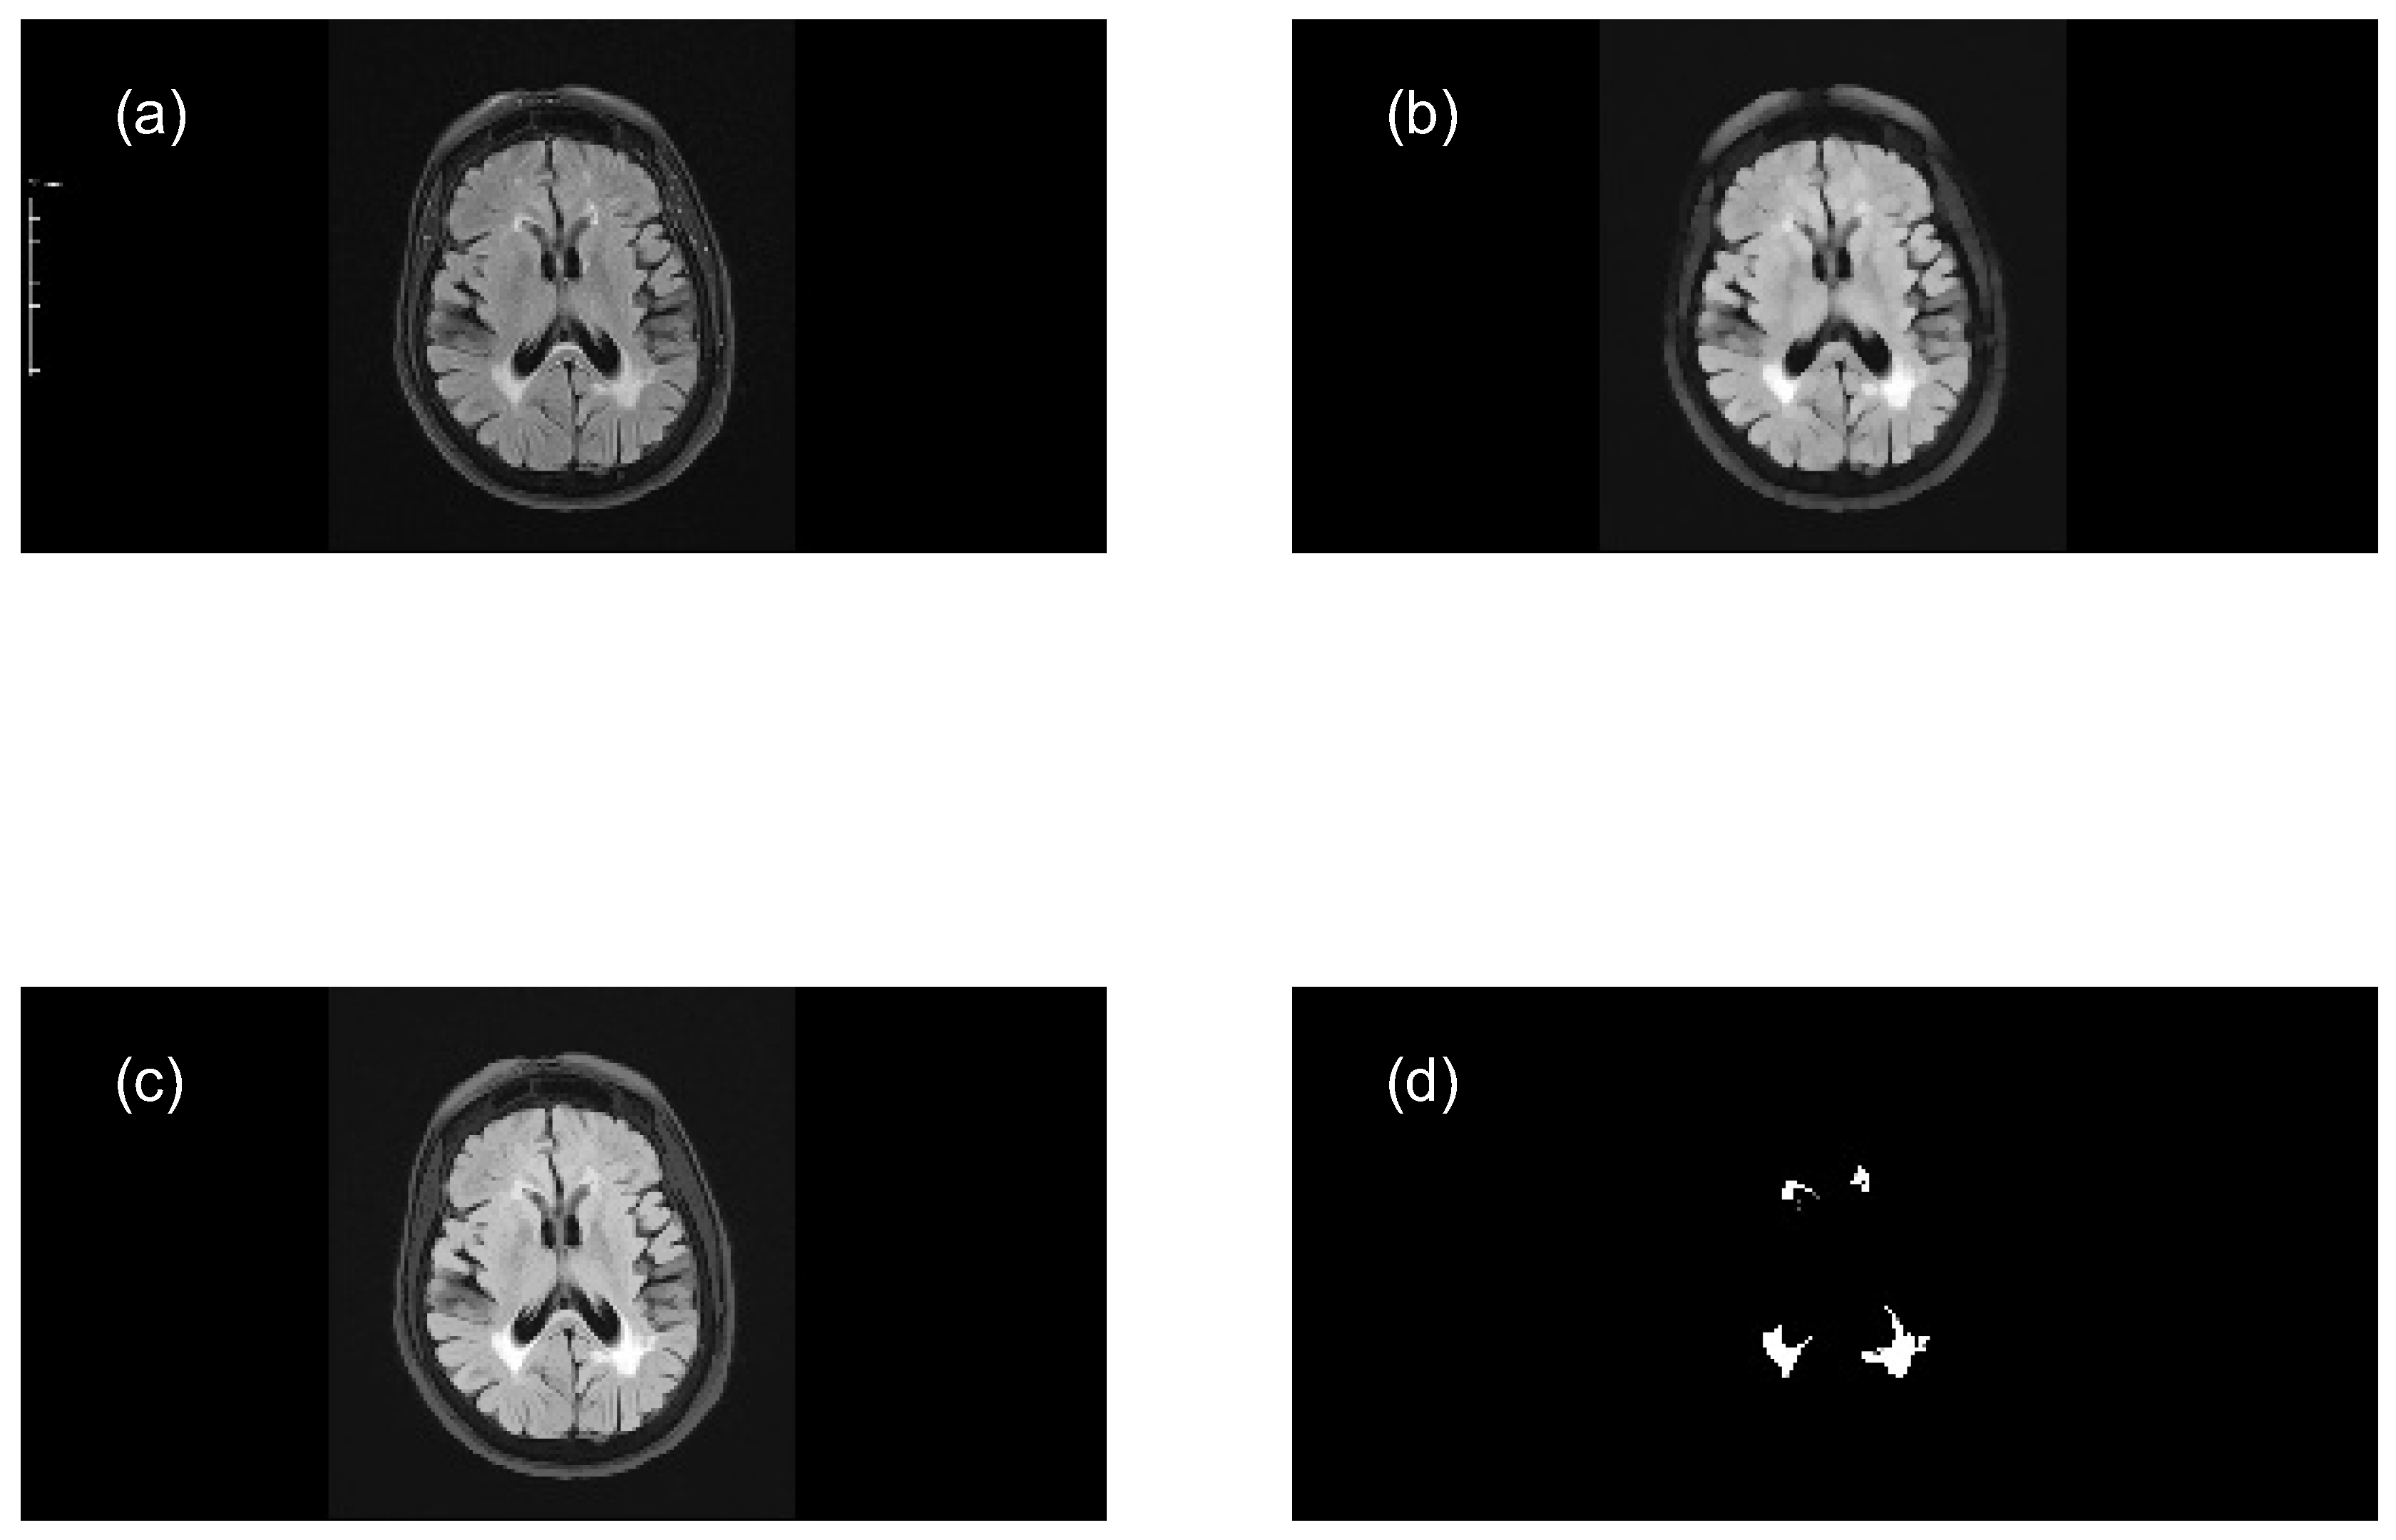

Perform opening morphological transformations on brain images of MS patients and healthy individuals (axial and sagittal MRI), compute the granulometry of objects (Equation 7), and use the resulting data to train two ANN models, applying the following steps:

- Read the original color image (.png) and convert it to grayscale (e.g. uint8 array 569x1158x3 → uint8 array 569x1158).

- Perform a morphological opening transformation on the image in grayscale (mask image) to create a marker image using a SE. This operation consists of an erosion followed by a dilation using the same SE. The created SE is disk-shaped with radius r, which matches the geometric properties of the relevant structures of a brain image.

- Perform an opening by reconstruction transformation on the mask image (Equation 5), using the marker image to identify high-intensity objects in the mask image.

- Adjust the intensity values of the opened image by reconstruction, which increases the contrast of the output image, to extract relevant structures (MS lesions).

- Compute the granulometry of objects of the opened image by reconstruction for different radius values () of the SE.